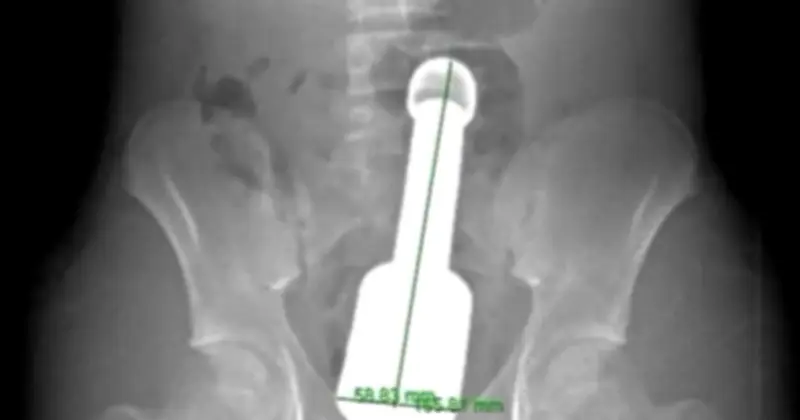

Dị Vật Kim Loại Kích Thước Đáng Kinh Ngạc

Hình ảnh y tế cho thấy chiếc chày kim loại có chiều dài lên tới 18 cm và đường kính 6 cm, một kích thước vượt quá giới hạn thông thường đối với cơ thể của một thiếu niên. Dị vật này không chỉ to mà còn rất nặng, đồng thời tạo ra hiệu ứng chân không phía trên đỉnh, khiến nó bị hút chặt vào lòng ruột, làm tăng nguy cơ biến chứng nghiêm trọng nếu xử trí không cẩn thận.